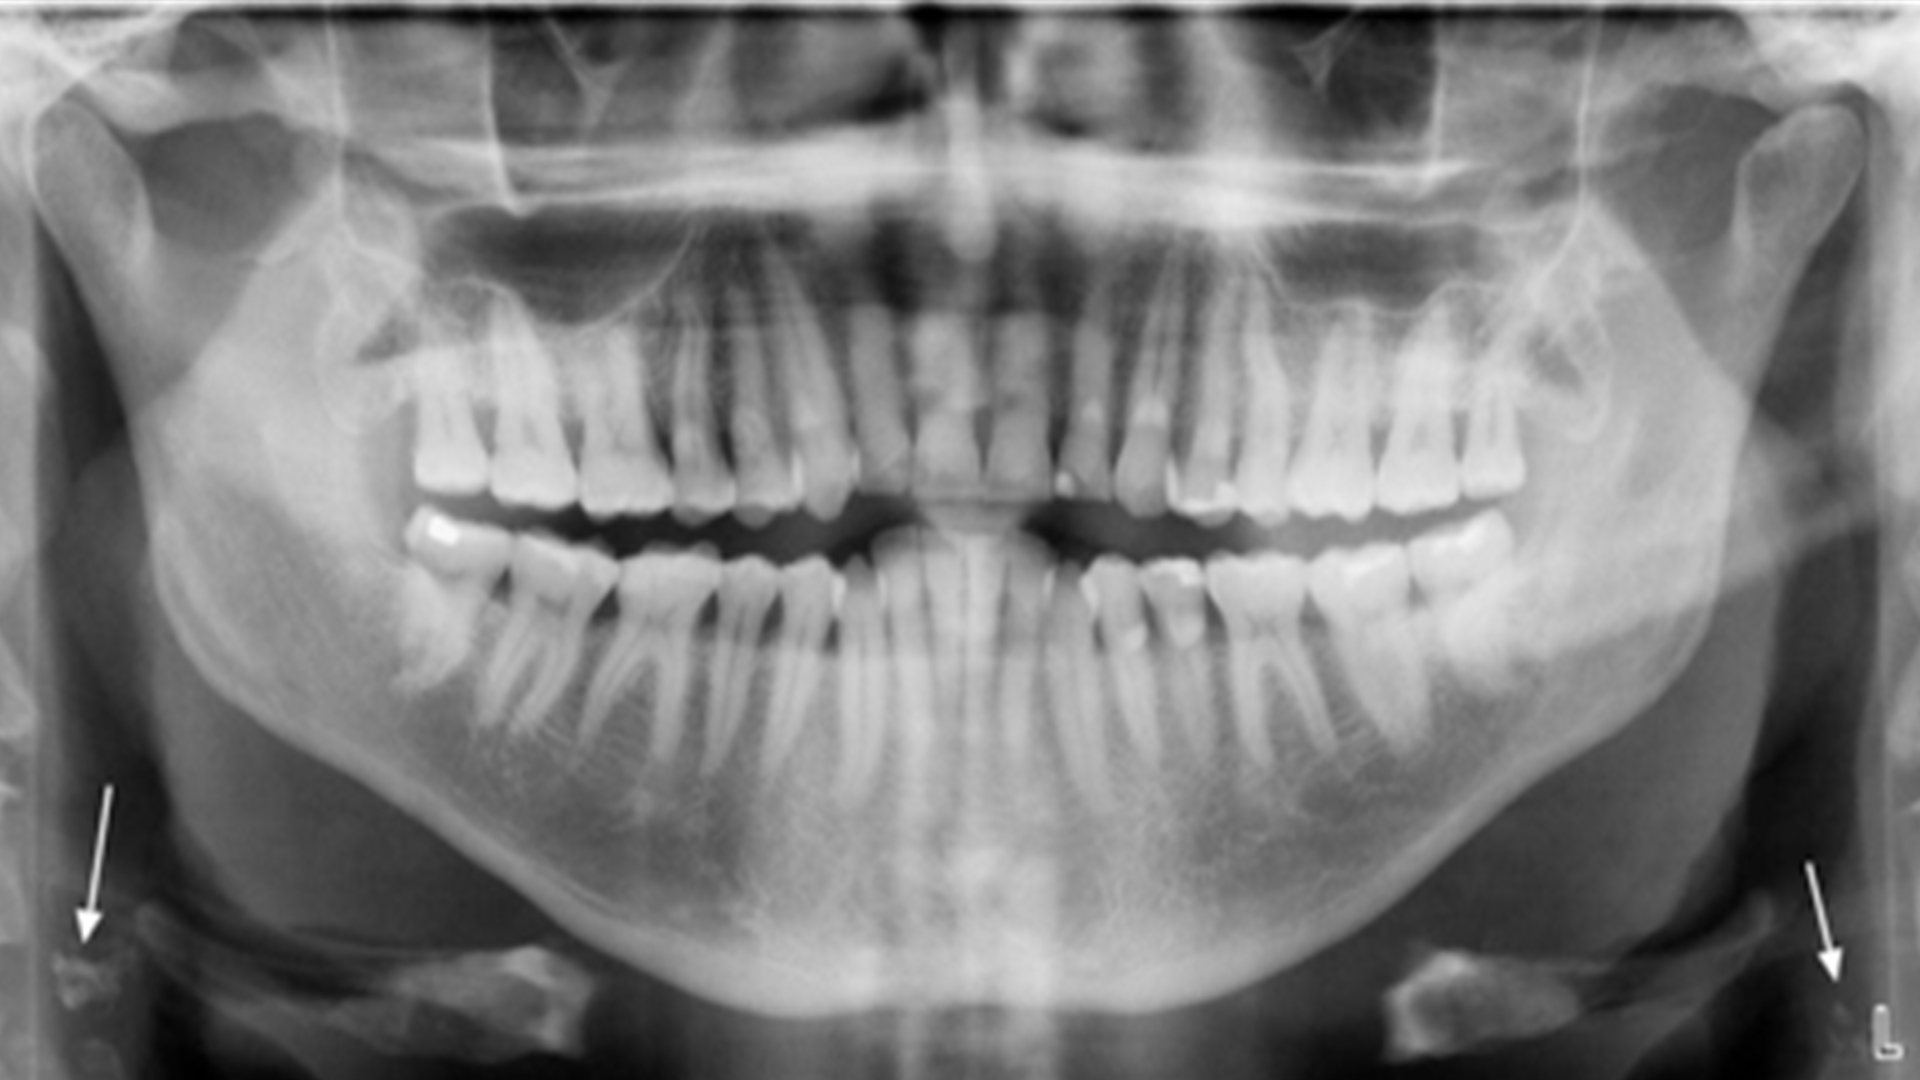

If a panoramic film is available, oral health care providers should examine these films for evidence of carotid calcifications. Identification of a suspected calcification should trigger questions to the patient, and likely a referral to a medical provider for further evaluation. Four examples of CCPR are provided in Figure 1.

Figure 1 (a-d): Examples of carotid calcifications detected on panoramic radiographs. Both standard (top) and enhanced (bottom) radiographs are provided. Digital enhancement is intended to improve visualization of the carotid calcifications, and is achieved with software provided by the manufacturer. Bilateral calcifications are present in all four patients (arrows).

69 year old male with a history of hypertension, type 2 diabetes, myocardial infarction, obstructive sleep apnea and a 60 pack-year smoking habit.